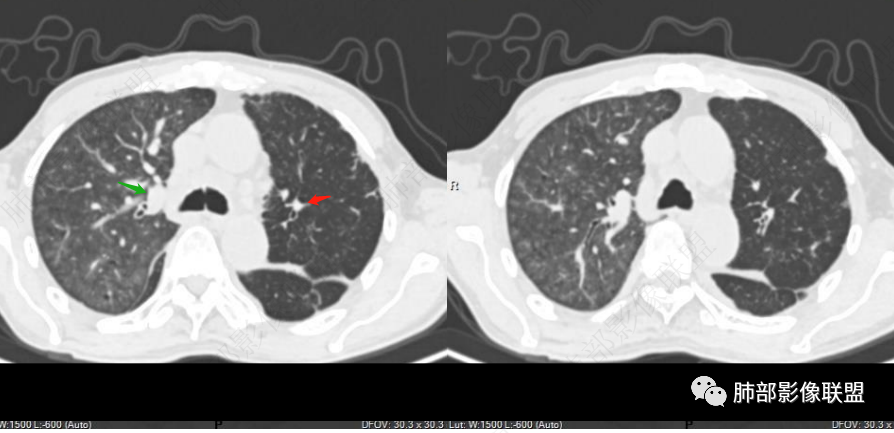

看一下影像,肺动脉粗大,大于升主动脉

一般认为升主动脉比肺动脉粗(同层)

从肺动脉的主体分析:左肺动脉好像起始部就开始狭窄。

现在给的图像:是鼠尾状狭窄,而不会局部膨隆,远端细小那种。

右侧的肺动脉增粗肯定与代偿有关。

现在的问题是自左肺动脉狭窄的原因:是急性栓塞?炎性病变?慢性血栓?

现在的影像改变提示:

1、陈旧结核

2、双侧胸水,小叶间隔光滑增厚——支持间质性肺水肿,提示心功能不全

3、右肺改变符合肺动脉高压导致

4、肺动脉改变:左肺动脉起始部突然狭窄(右肺动脉代偿增大——继发肺内改变)

南边:

就是根源还是与左肺动脉起始部狭窄相关性大。

无非:急性栓塞、慢性栓塞、炎症、肿瘤。

目前的依据,我觉得急性栓塞的特点不太明显啊。

7.肺动脉主干扩张,左侧肺动脉主干见混杂密度影,上下肺动脉似不能连续追踪。

(增强:左肺动脉充盈缺损、闭塞)

5.影像左肺动脉栓塞、闭塞——上下肺动脉以远相对纤细——左肺动脉“断供”,且存在支气管动脉扩张可能。